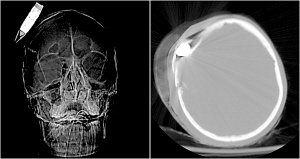

上个月美国驻阿富汗巴格拉姆空军基地医院收治了一名20多岁的阿富汗士兵,他头部中弹。医生原本以为这是战场上常见的外伤,嵌入士兵头皮中的异物可能只是一块碎裂的弹片。然而CT扫描结果显示,该口径为14.5毫米的“弹片”竟是一枚尚未爆炸的高爆炸弹,内部至少含有2盎司高纯炸药。

据悉,这枚高爆炸弹从伤者的头皮穿入,深深嵌入其右侧大脑。“全副武装”的比尼医生动作娴熟地切开了伤者的头皮,在嵌入的高爆炸弹四周做了一个巨大的环状切口。经过10分钟小心翼翼的操作,他终于将那枚随时可能爆炸的高爆炸弹取了出来。拆弹小组将炸弹装入一个特制的包装袋,在安全的地方引爆。